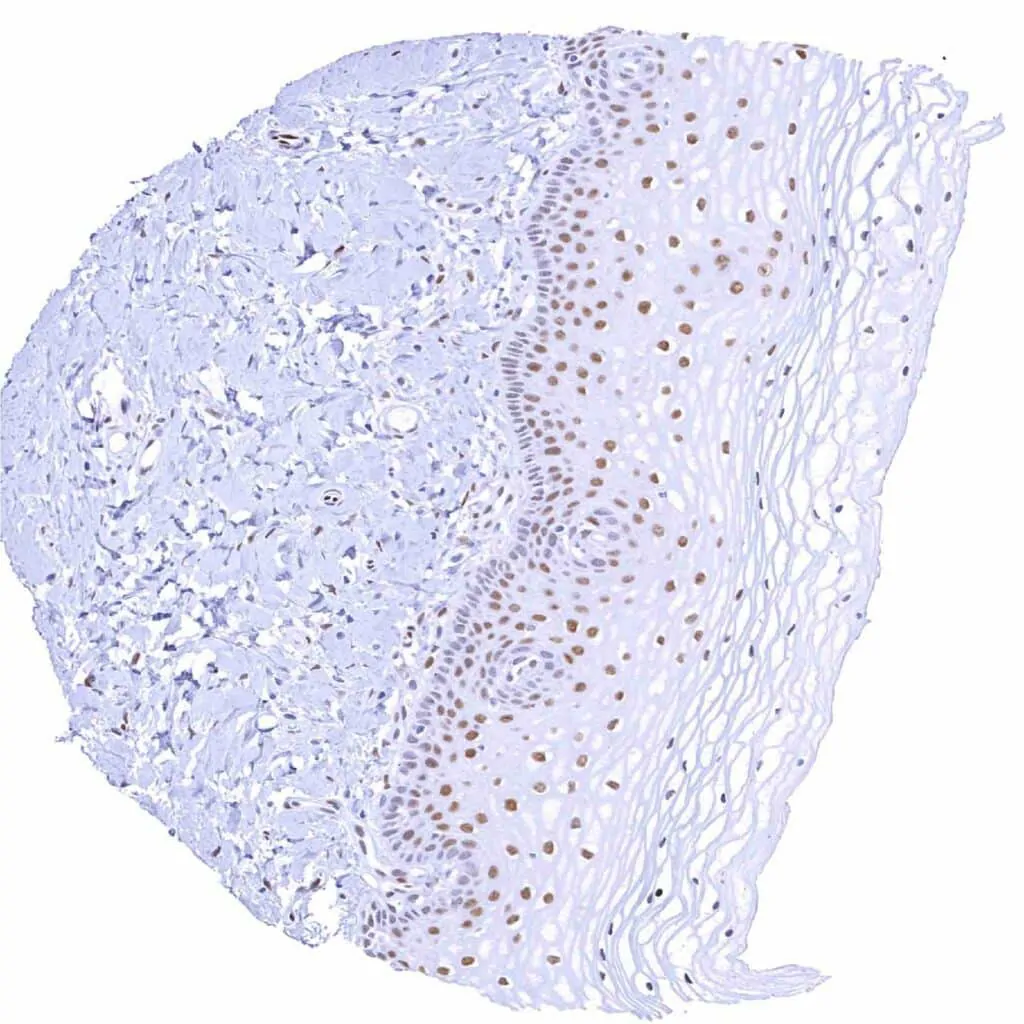

Esophagus, squamous epithelium – Weak TLE1 staining of a subset of lymphocytes and of the squamous epithelium, predominantly of the suprabasal cell layers